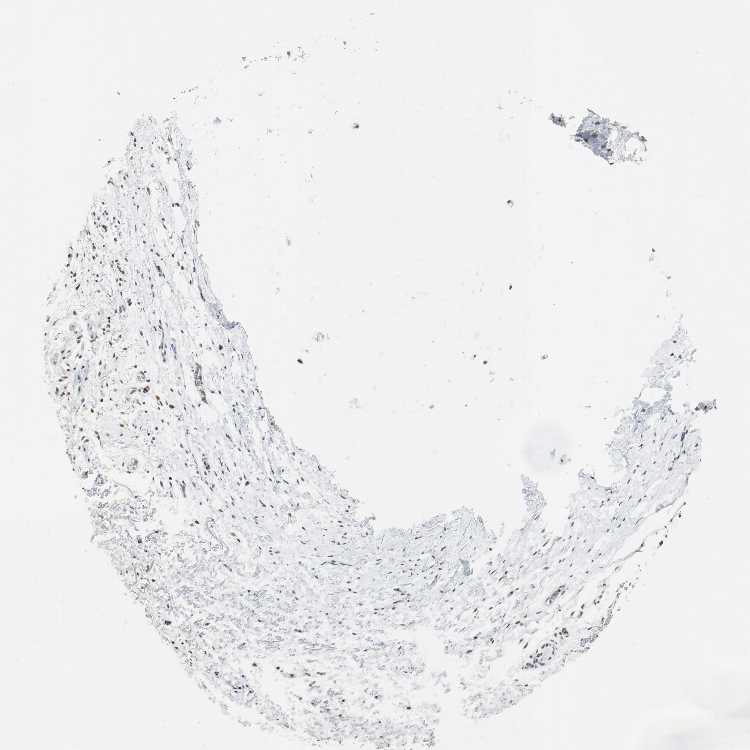

TISSUE PRIMARY DATA SOFT TISSUE Show tissue menu

SOFT TISSUE - Expression summary

SOFT TISSUE 2 - Antibody stainingi

Antibody staining in the annotated cell types in the current human tissue is reported as not detected, low, medium, or high, based on conventional immunohistochemistry profiling in selected tissues. This score is based on the combination of the staining intensity and fraction of stained cells.

Each image is clickable and will lead to virtual microscopy that enables deeper exploration of all samples and also displays staining intensity scores, fraction scores and subcellular localization as well as patient and tissue information for each sample.

Antibody HPA002694Antibody CAB005876

Fibroblasts Not detectedLow

Peripheral nerve Not detected-